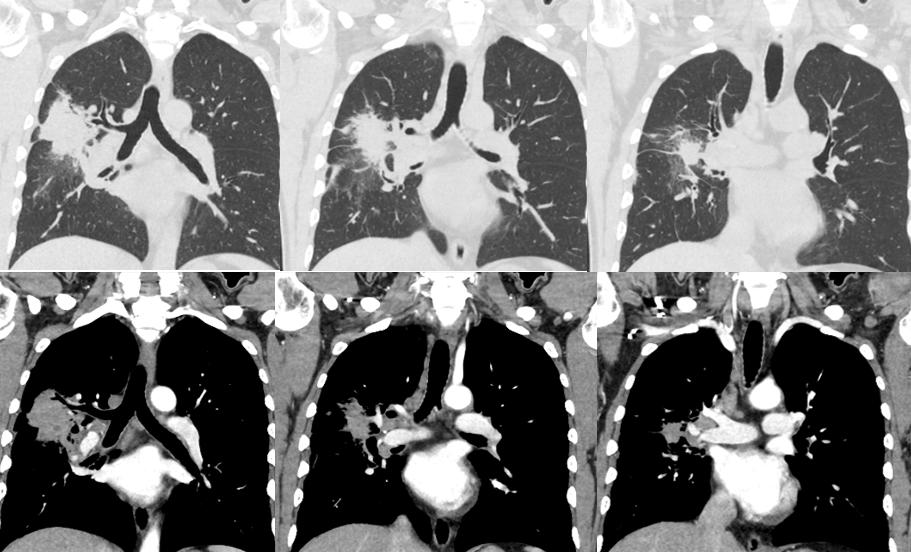

病例二

病史:女性,70岁。主诉:查体发现右肺上叶占位1周余。

影像描述:右肺上叶尖段见一不规则形混合磨玻璃密度灶,大小约 .7X4.2X4.5m,内可见多发小空腔中央部分较密实,周边可见斑片状密度增高影及毛刺,边界不清,邻近胸膜受牵拉,增强扫描实性成分可见强化:双肺另见多发点状结节灶,边界尚清,增强扫描未见明显强化。左肺上叶舌段见条索状密度增高灶,邻近胸膜受牵拉。段及以上支气管通畅。食管胸下段、胃责门及小弯侧胃壁略显增厚。纵隔内未见异常增大的淋巴结。双侧胸腔未见明显液性密度灶。

影像诊断:右肺上叶混合磨玻璃灶,鉴别于肺癌与机化性肺炎,建议病理学检查:双肺多发点状结节灶,建议随诊复查:

病理:腺癌。